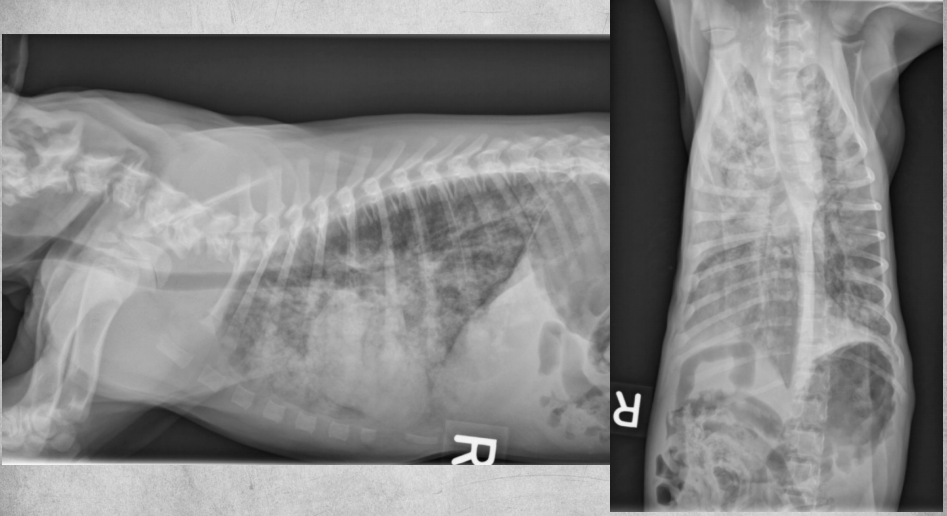

● 12 yo male castrated Shih-Tzu

● Geriatric check-up

● No clinical signs

congenital peritoneal-pericardial diaphragmatic hernia

these intestines are filled with gas due to

being empty

gastric axis also altered